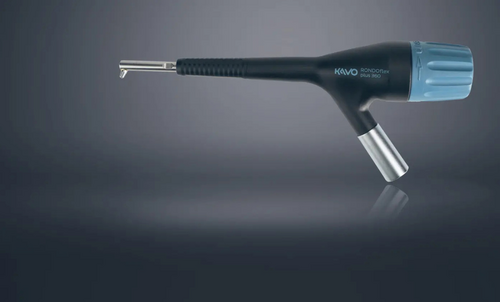

La fase successiva è poi quella della strumentazione4 : sul manipolo ultrasonico è possibile montare le diverse punte per la strumentazione sia sopragengivale (NSK ‘Gingival’), che sottogengivale (NSK ‘Periodontal’), selezionando il programma in uso (sopragengivale, sottogengivale o ad ultrasuoni), il livello di potenza (10 livelli) ed il

volume dell’acqua, per rendere sempre più personalizzato il trattamento dei nostri pazienti. (FIG.3)

L’ultimo modello proposto dall’azienda NSK è il “VARIOS COMBI PRO”.

La Varios Combi Pro NSK permette al clinico di lavorare in maniera confortevole sfruttando le varie funzioni di trattamento ultrasonico ed air polishing per applicazioni sopragengivali e sottogengivali, garantendo un efficace controllo del biofilm ed un'accurata igiene professionale.